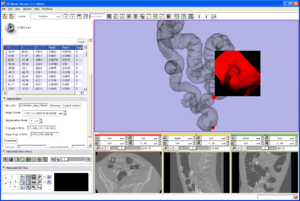

An Open Tool for Input Function Estimation and Quantification of Dynamic PET FDG Brain Scans

Publication: Int J Comput Assist Radiol Surg. 2015 Oct 29. PMID: 26514683 Authors: Bertrán M, Martínez N, Carbajal G, Fernández A, Gómez Á. Institution: Instituto de Ingeniería Eléctrica, Facultad de Ingeniería, Universidad de la República, Montevideo, Uruguay. Background/Purpose: Positron emission tomography (PET) analysis of clinical studies is mostly restricted to qualitative evaluation. Quantitative analysis of PET studies is highly desirable to be able to compute an objective measurement of the process of interest in order to evaluate treatment response and/or compare patient data. But implementation of quantitative analysis generally requires the determination of the input function: the arterial blood or plasma activity which indicates how much tracer is available for uptake in the brain. The purpose of our work was to share with the community an open software tool that can assist in the estimation of this input function, and the derivation of a quantitative map from the dynamic PET study. Methods: Arterial blood sampling during the PET study is the gold standard method to get the input function, but is uncomfortable and risky for the patient so it is rarely used in routine studies. To overcome the lack of a direct input function, different alternatives have been devised and are available in the literature. These alternatives derive the input function from the PET image itself (image-derived input function) or from data gathered from previous similar studies (population-based input function). In this article, we present ongoing work that includes the development of a software tool that integrates several methods with novel strategies for the segmentation of blood pools and parameter estimation. Results: The tool is available as an extension to the 3D Slicer software. Tests on phantoms were conducted in order to validate the implemented methods. We evaluated the segmentation algorithms over a range of acquisition conditions and vasculature size. Input function estimation algorithms were evaluated against ground truth of the phantoms, as well as on their impact over the final quantification map. End-to-end use of the tool yields quantification maps with relative error in the estimated influx versus ground truth on phantoms. CONCLUSIONS: The main contribution of this article is the development of an open-source, free to use tool that encapsulates several well-known methods for the estimation of the input function and the quantification of dynamic PET FDG studies. Some alternative strategies are also proposed and implemented in the tool for the segmentation of blood pools and parameter estimation. The tool was tested on phantoms with encouraging results that suggest that even bloodless estimators could provide a viable alternative to blood sampling for quantification using graphical analysis. The open tool is a promising opportunity for collaboration among investigators and further validation on real studies. |